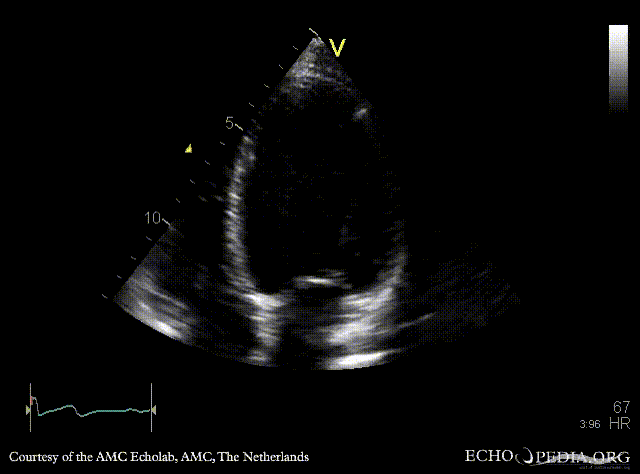

A4CH: Color Doppler, moderate mitral regurgitation